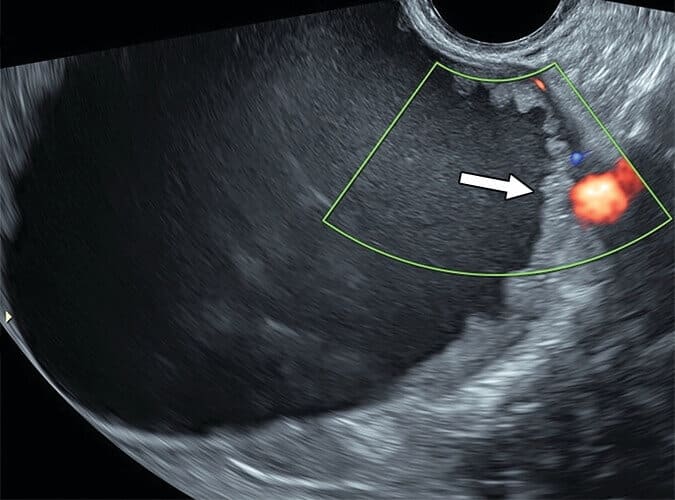

Cisto unilocular com componentes sólidos

Nos cistos uniloculares que apresentam componente sólido, a classificação entre O-RADS 4 e O-RADS 5 depende principalmente do número de projeções papilares, estruturas sólidas que estendem-se para dentro do cisto com pelo menos 3 mm e são totalmente banhadas por líquido em três lados.

Lesões que exibem até três projeções papilares, ou um componente sólido que não se enquadra como projeção papilar, classificam-se como O-RADS 4. Já quando há quatro ou mais projeções papilares, o risco de malignidade aumenta, elevando a classificação para O-RADS 5.